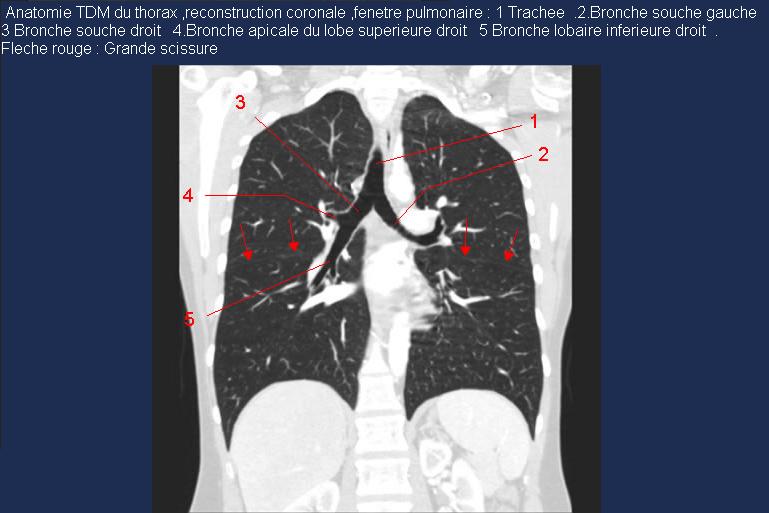

Radioanatomie pulmonaire ( image radiologie thoracique normale )- La Tomodensitometrie du  thorax ( coupes coronales fenetre pulmonaire )

Les fenetres parenchymateuses permettre d'etudier anatomie du poumon et juger sur les lesions du parenchyme pulmonaire en coupes axiales de 0,5-1cm sur le thorax .